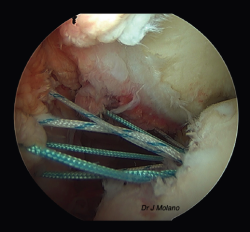

Posteriormente, se realiza el remplissage por vía artroscópica. Se coloca el artroscopio en el portal anterosuperior y se emplean el anterior y el posterior como portales de trabajo. Desde el portal posterior se realiza el curetaje/raspado superficial de la lesión de Hill-Sachs para conseguir una superficie sangrante. Tras ello, se colocan 2 implantes de tipo Iconix® (Stryker, Kalamazoo, MI, USA) (cargados con 2 hilos de sutura cada uno) desde el portal posterior próximos a la parte más medial del defecto de Hill-Sachs. Se recupera cada cabo de sutura de manera independiente a través del tejido capsular/infraespinoso con una pinza grasper, quedando estos en la misma línea mediolateral para ser anudadas sobre el infraespinoso al final del tiempo artroscópico(14) (Figuras 2 y 3).

Figura 3. Visión artroscópica desde el portal superior de un hombro derecho. Se observa Hill-Sachs tras pasar las suturas de remplissage, antes del anudado final.